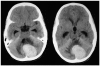

Case report: We report herein a case of melanotic or pigmented choroid plexus carcinoma in the posterior fossa of an 11-year-old female.